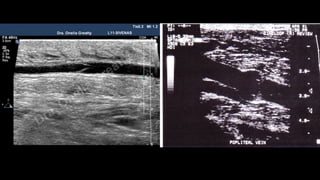

• Vena poplítea:

vPosición posteromedial:

vEje longitudinal de la VP, ascendiendo al canal aductor hasta la parte distal de

la VFS.

vSuperficial a la arteria poplítea.

vContinuar distalmente hasta la bifurcación (troncos tibial posterior y

peroneal).

vEje transversal: comprobar compresibilidad.

• Vena poplítea: vPosiciónposteromedial: vEje longitudinal de la VP, ascendiendo al canal aductor hasta la parte distal de la VFS. vSuperficial a la arteria poplítea. vContinuar distalmente hasta la bifurcación (troncos tibial posterior y peroneal). vEje transversal: comprobar compresibilidad.